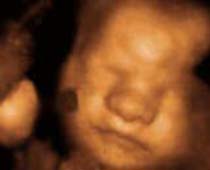

- Fetal Face Ultrasound Photos

- 3D Fetal Profile Ultrasound Scan Photos

- The Clinical Advantages of 3D and 4D Ultrasound

- Definition and Features of Four Dimensional Ultrasound

- Uses of 4D Ultrasound scan